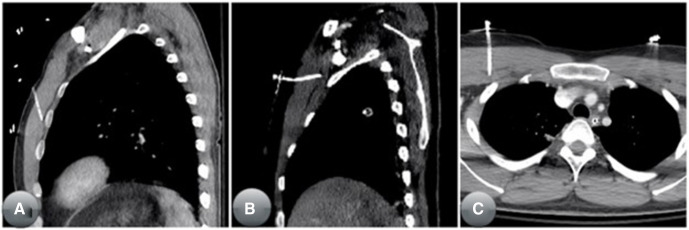

이전 연구들과 마찬가지로 NT 삽입 실패에 기여하는 요인은 복합적이며, 일부 사례는 그림 3에 제시되어 있다. 이러한 결과는 시뮬레이션이나 사체 실습과 같은 기법을 활용한 병원 전 인력의 강화된 훈련이 성과 향상에 고려되어야 함을 시사한다. Grabo 등 21은 구급대원이 사체를 활용한 훈련을 받았을 때 NT 성공률이 75%였으며, 전통적인 슬라이드와 강의 방식으로 훈련받았을 때의 35%보다 훨씬 높았다고 보고했다. 또한 최근 시뮬레이션 모델과 기법의 발전은 침습적 의료 기술 훈련을 크게 향상시켰다 22. 더불어 응급의료기관의 의료 책임자, 권역외상센터, 필요 시 검시관으로부터 지속적이고 건설적인 수행 피드백이 필요하다.